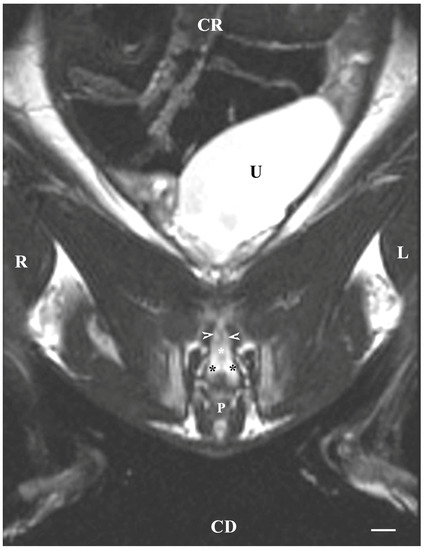

3.1. Subsection Transverse MRI Visualization

On transverse T2-weighted imaging in the corresponding planes (first caudal vertebra, then the plane between the first and second caudal vertebrae—dorsal; the caudal part of the pelvic symphysis—ventral; the plate of ischium—lateral), the rabbit bulbourethral glands were identified. They appeared as soft-tissue, homogeneous organs with hyper-intense characteristics compared to the peripheral soft tissue landmarks (urethra, rectum, pelvic diaphragm), except for the penile bulb and the beginning of the penile root. The latter were visualized as findings with the highest intensity relative to structures in the perineum. The shape of the glands was oval. The glandular capsule was differentiated as a hypo-intense peripheral ring-like finding. The ventrally located pelvic part of the urethra was hypo-intense and imaged dorsally to the caudal part of the pelvic symphysis. The rectum showed a hypo-intense image that was localized dorsally to the penile bulb and root and ventrally to the first caudal vertebra (Figure 1).

Figure 1. T2-weighted transverse image of rabbit pelvis in the plane through the level of the first caudal vertebra (white star): R—right; L—left. Bulbourethral glands (white horizontal arrows), the pelvic part of the urethra (white cross), penile bulb (B), rectum (R), ischial bones (black stars), the caudal part of the pelvic symphysis (white perpendicular arrow), pelvic diaphragm (black inclined arrows), and testes (T). Line—10 mm.

On transverse MRI in a T1-weighted sequence of the pelvis, planes through the following bone anatomical landmarks were used: the first and second caudal vertebrae, dorsally, the caudal part of the pelvic symphysis, ventrally, and the plate of the ischium, laterally. The bulbourethral glands were difficult to identify. They were visualized as soft-tissue, homogeneous findings with an intermediate characteristic compared to the peripheral organs (urethra, rectum, pelvic diaphragm). The shape of the glandular findings was not clearly defined. Each of the glands was imaged independently of the adjacent structures but with indistinct organ boundaries, capsules and parenchyma. The ventromedial pelvic part of the urethra was hypo-intense and visualized dorsally to the caudal part of the pelvic symphysis but without any clear definition of the studied glandular structures. The urethral lumen was hypo-intense relative to the urethral wall. The lumen of the rectum was the most hypo-intense finding compared to the rest of the organs in the perineum (Figure 2 and Figure 3).

Figure 2. T1-weighted transverse image of rabbit pelvis at the level of the first caudal vertebra (black star): R—right; L—left. Bulbourethral glands (white horizontal arrows), the pelvic part of the urethra (black cross), penile bulb and penile root (B), rectum (R), ischial bones (white stars), the caudal part of the pelvic symphysis (white perpendicular arrow), pelvic diaphragm (black perpendicular arrow), and testes (T). Line—10 mm.

Figure 3. T1-weighted transverse image of rabbit pelvis through the level of the second caudal vertebra (white star): R—right; L—left. Bulbourethral glands (white horizontal arrows), the pelvic part of the urethra (white cross), penile bulb (B), rectum (R), ischial bones (black stars), the caudal part of the pelvic symphysis (white perpendicular arrow), pelvic diaphragm (black perpendicular arrow), and testes (T). Line—10 mm.